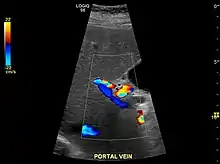

Ultrasound is routinely used in the evaluation of cirrhosis.[36] It may show a small and shrunken liver in advanced disease. On ultrasound, there is increased echogenicity with irregular appearing areas.[54] Other suggestive findings are an enlarged caudate lobe, widening of the fissures and enlargement of the spleen.[55] An enlarged spleen, which normally measures less than 11–12 cm in adults, may suggest underlying portal hypertension.[56] Ultrasound may also screen for hepatocellular carcinoma and portal hypertension.[36] This is done by assessing flow in the hepatic vein.[57] An increased portal vein pulsatility may be seen. However, this may be a sign of elevated right atrial pressure.[58] Portal vein pulsatility are usually measured by a pulsatility indices (PI).[57] A number above a certain values indicates cirrhosis (see table below).